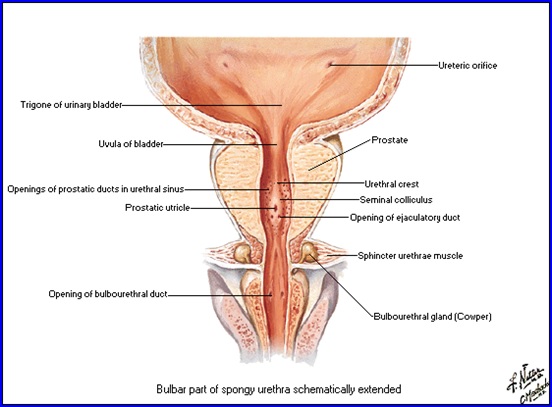

Prostata

Glandă situată în spaţiul pelvisubperitoneal, sub vezica urinară dezvoltată în jurul porţiunii iniţiale a uretrei masculine.

Formă de con cu baza spre vezică.

Dimensiuni: 4/3/3cm.

Loja prostatică:

- Anterior: oasele pubiene;

- Posterior: septul rectovezical Denonvilliers;

- Iinferior: diafragma urogenitală;

- Superior: lig. pubo-prostatice, fundul vezicii, ductele deferente, veziculele seminale.

Vascularizaţie:

- Arterială: din aa. vezicale inferioare, rectale mijlocii şi ruşinoase interne.

- Venoasă: venele prostatei drenează în plexul venos periprostatic care are conexiuni cu v. dorsală profundă şi v. hipogastrică